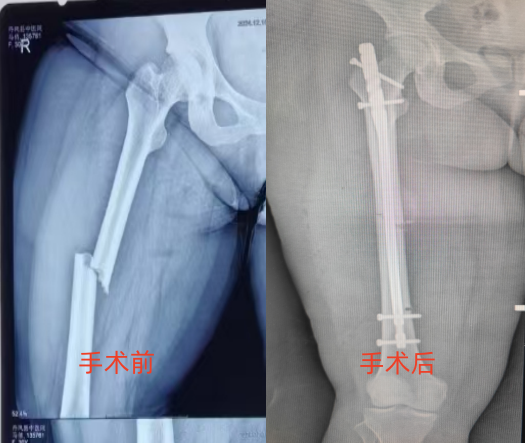

近日,在多学科团队的护航下,丹凤县医院副院长程涛、骨二科副主任李静宏及副主任医师何正位带领团队克服重重困难,成功为一名体重高达280斤的重度肥胖患者实施了股骨干骨折闭合复位髓内钉术。

患者王某,30岁,体重近280斤,走路时不慎跌倒致左股骨干骨折,由于体重太重,其他几家医院均表示医疗条件无法实行手术,于是慕名来到我院骨二科寻求进一步诊治。接诊后,骨二科副主任李静宏表示:“为这样一位“重量级”患者实施手术,对医生和患者本人来说,无疑是一场巨大的考验”。

采取何种手术方式是一大难题,程涛院长介绍,如果采用传统的股骨干手术,切口长约15cm,创口大。王某体重达280斤,皮下脂肪厚,术后极易出现脂肪液化、切口感染、骨不连等严重并发症。综合各项因素后,进行多次术前讨论,研究手术预案,最终选择为股骨干骨折闭合复位髓内钉术,这样的创口小,恢复快,同时降低了术中和术后感染发生率,而且瘢痕也小,外观更美观。

为确保手术万无一失,术前,骨二科与手术室、麻醉科对患者病情进行充分讨论,制定了周密的手术和麻醉方案。手术过程和术前预料的一样困难,仅仅摆放体位就用了大约30分钟,切开皮肤后脂肪层有8cm厚,患者的肌肉也比较粗壮,切开皮肤后十几厘米都看不到骨头,术中由2位医生轮流抱着病人的患肢,才保证手术的顺利实施。骨折复位后需要用床边透视机检查骨折复位情况,因为患者体胖,拍摄正侧斜位片时很难把机器摆放到合适的体位,要不停地升降手术台才能完成。最终,由程涛院长、李静宏主任、何正位副主任医师勠力同心,历时2小时,顺利为患者完成了手术,术中X线片显示骨折解剖复位、固定可靠,手术十分成功。术后一周,患者伤口恢复良好,可扶助行器下床行走,目前,患者已顺利出院。![]()